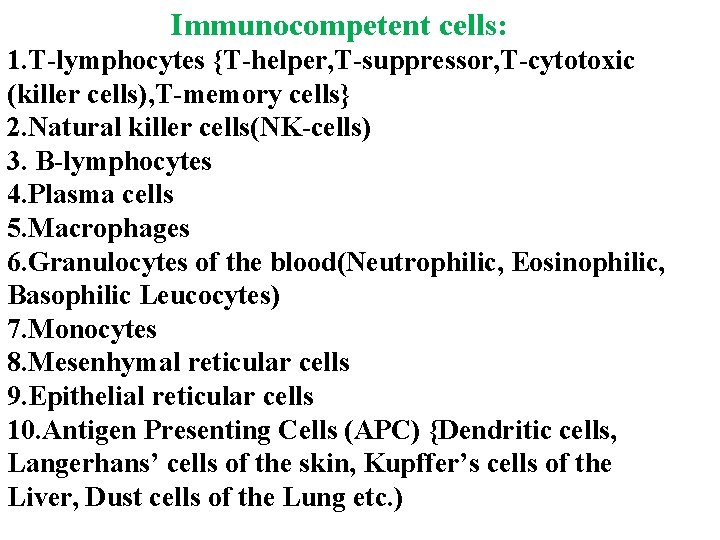

Immunocompetent cells: 1. T-lymphocytes {T-helper, T-suppressor, T-cytotoxic (killer cells), T-memory cells} 2. Natural killer cells(NK-cells) 3. B-lymphocytes 4. Plasma cells 5. Macrophages 6. Granulocytes of the blood(Neutrophilic, Eosinophilic, Basophilic Leucocytes) 7. Monocytes 8. Mesenhymal reticular cells 9. Epithelial reticular cells 10. Antigen Presenting Cells (APC) {Dendritic cells, Langerhans’ cells of the skin, Kupffer’s cells of the Liver, Dust cells of the Lung etc. )